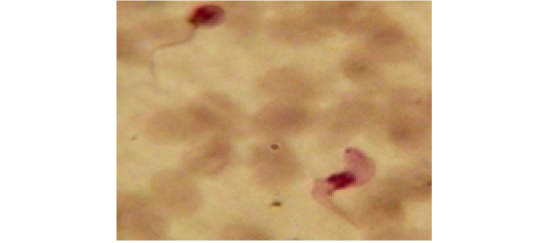

Showing long slender form of T. evansi in examined camel (x 1000).